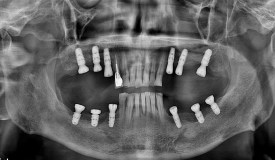

<혈전제 복용 환자로 복용약 중단을 최소화하고

의식하진정요법을 통해 위/아래 두 번만에 수술 후 보철 완료 사례>

저희는 의식하진정요법을 활용해 한 번의 수술로 많은 임플란트를 심을 수 있어 환자의 부담을 줄일 수 있는데요.

의식하진정요법은 잠을 자는 것처럼 긴장을 완화하고 편안한 상태에서 받을 수 있고, 이는 회복에도 긍정적인 영향을 줍니다.